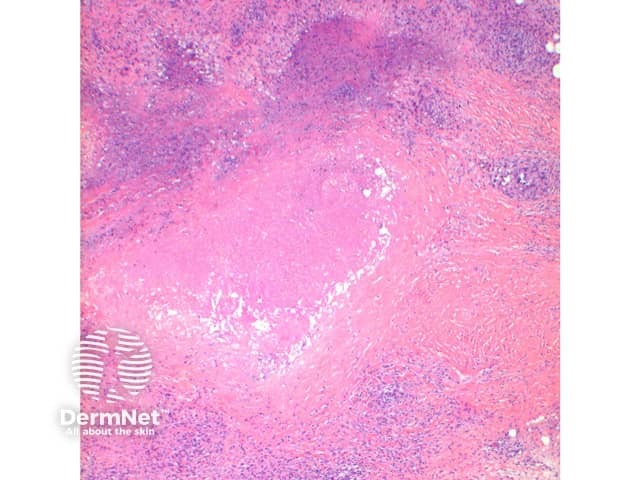

Figure 3

The scanning view of the histology of granuloma annulare shows a granulomatous inflammatory pattern situated within the superficial and mid dermis.